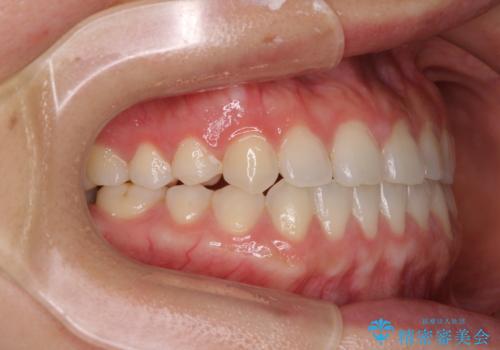

- 上下の前歯の隙間を気にして来院された患者様です。

インビザラインを用い、上下歯列のスペースを閉じていくこととしました。

治療期間中は奥歯がほとんど咬めない状態が続き、食事に大変苦労されました。

最終的には隙間もしっかりと閉じ、奥歯も咬みやすい状態でしあげることができました。